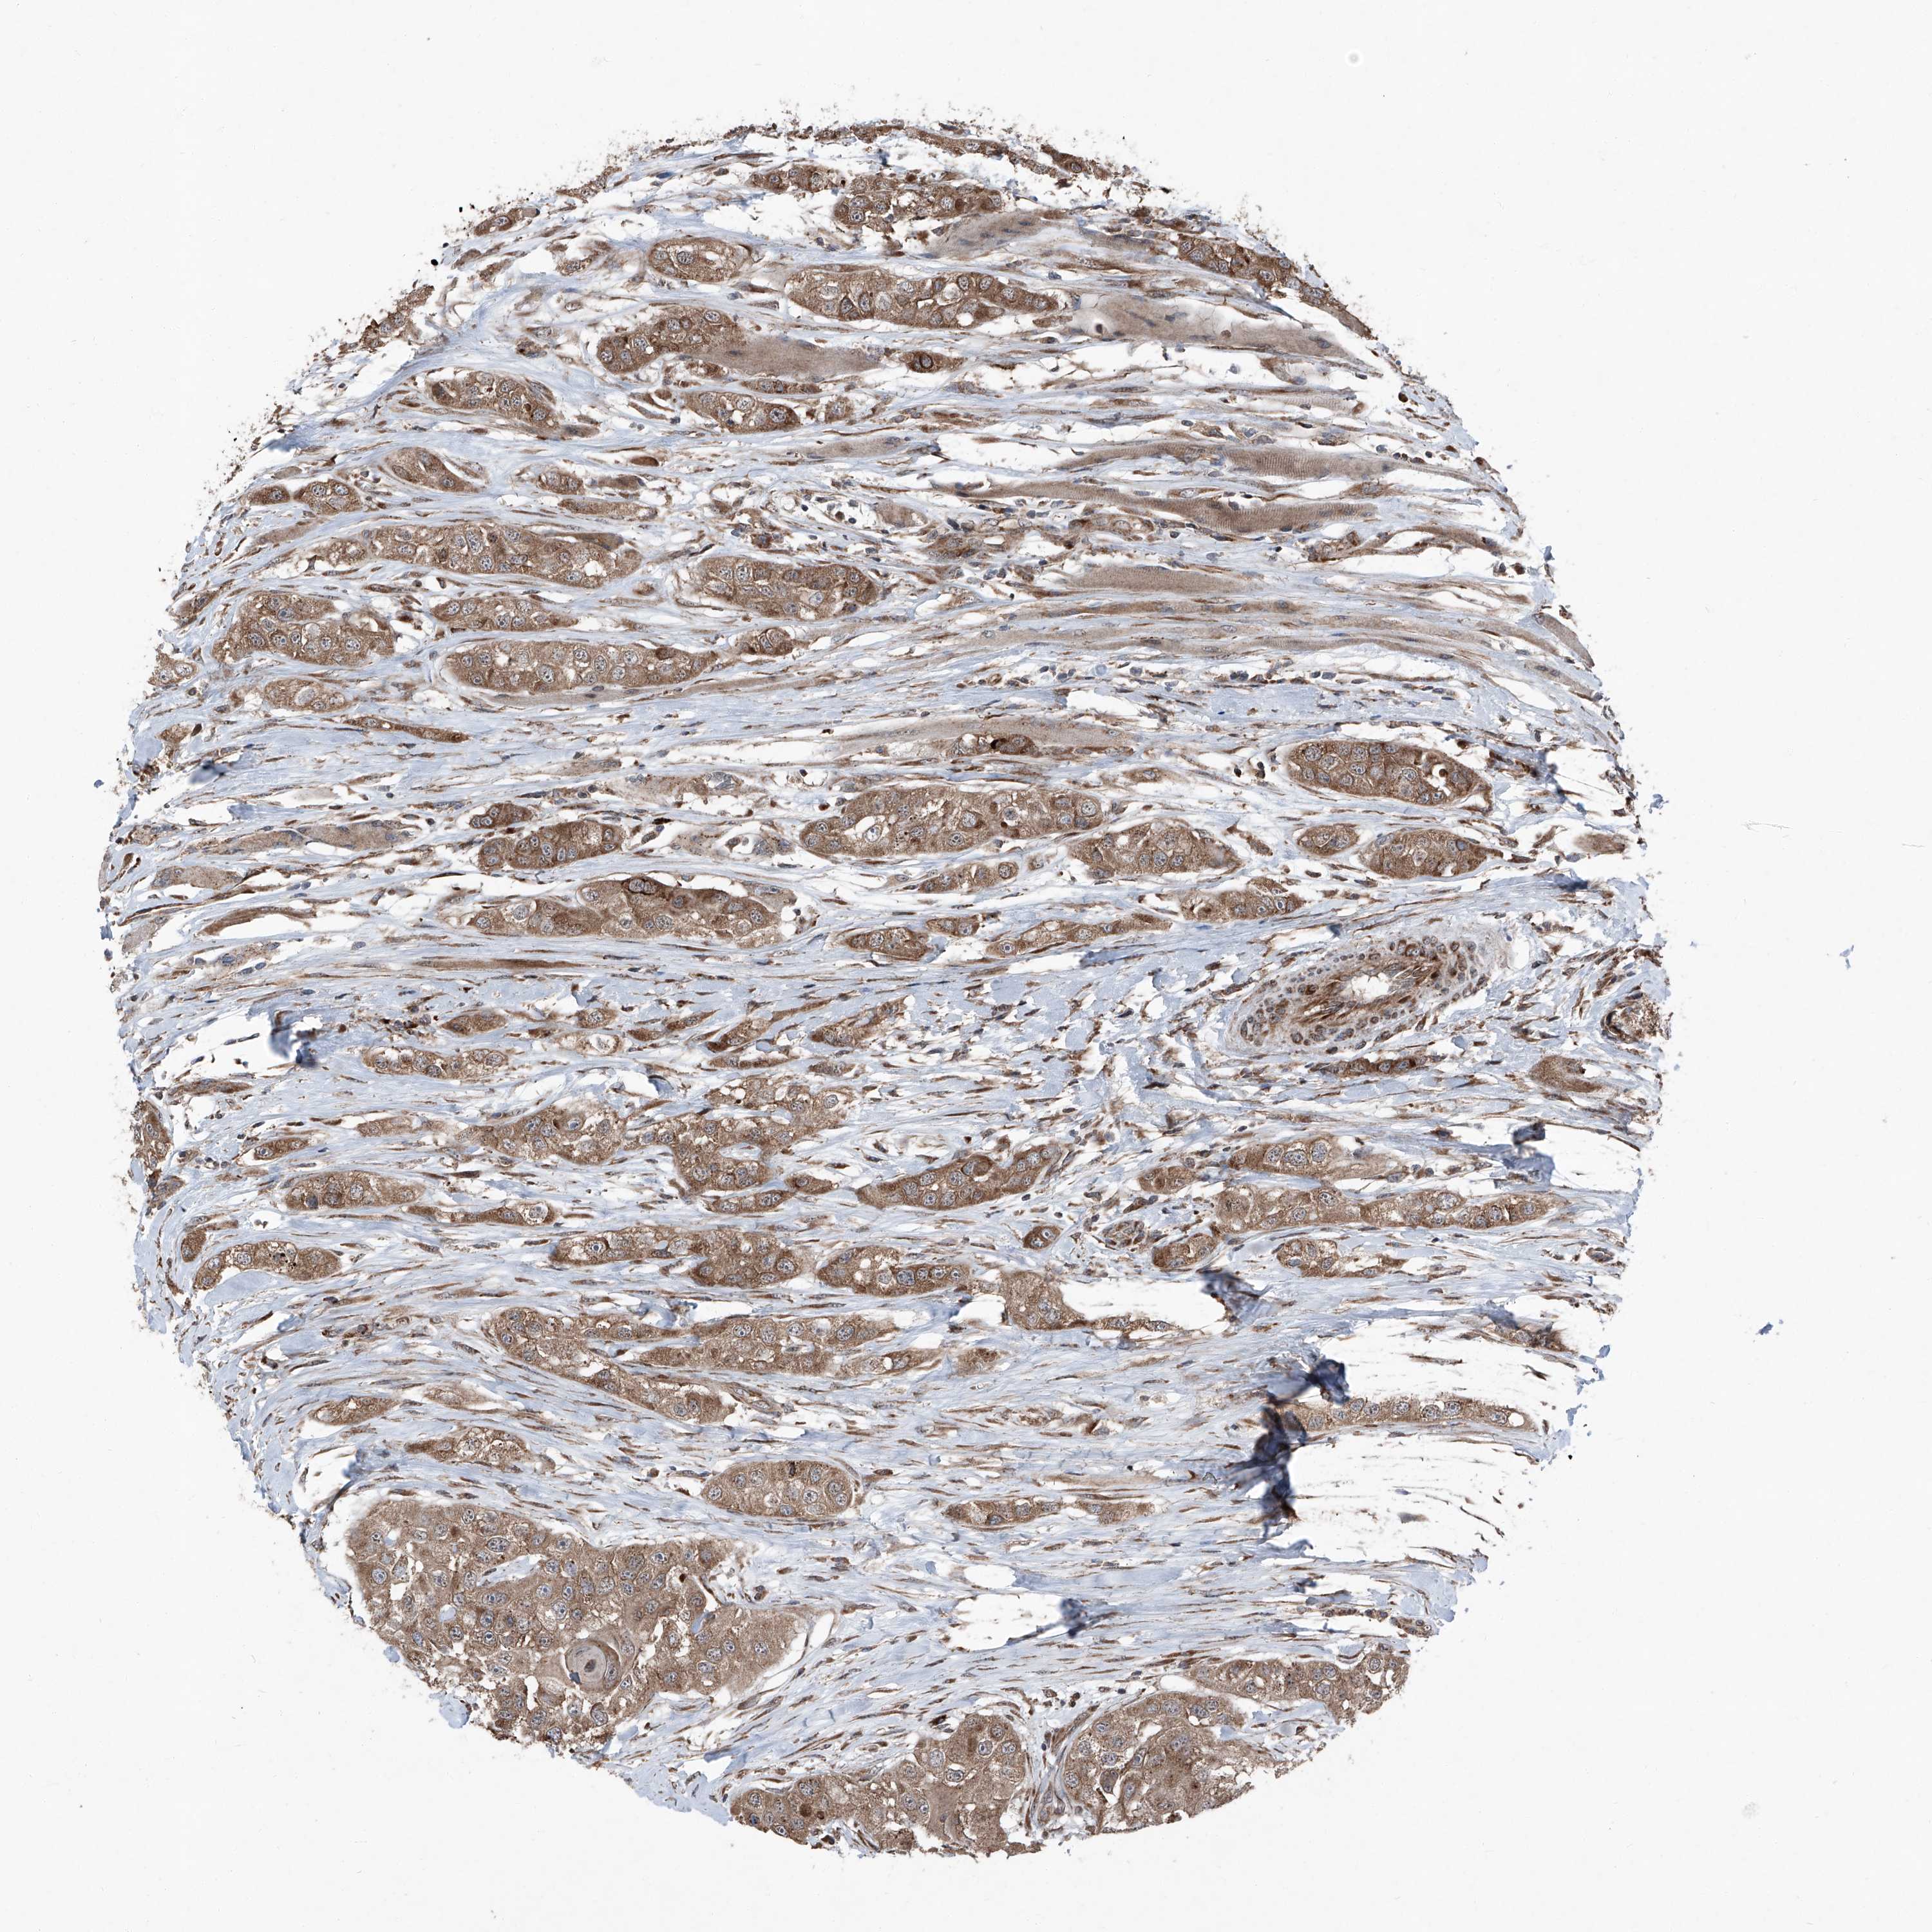

HEAD AND NECK CANCER - Protein expressioni

A mouse-over function shows sample information and annotation data. Click on an image to view it in a full screen mode. Samples can be filtered based on level of antibody staining by selecting one or several of the following categories: high, medium, low and not detected. The assay and annotation is described here.

Antibody stainingi

Antibody staining in the annotated cell types in the current human tissue is reported as not detected, low, medium, or high, based on conventional immunohistochemistry profiling in selected tissues. This score is based on the combination of the staining intensity and fraction of stained cells.

Each image is clickable and will lead to virtual microscopy that enables deeper exploration of all samples and also displays staining intensity scores, fraction scores and subcellular localization as well as patient and tissue information for each sample.

Antibody HPA028516

Staining

High

Medium

Low

Not detected

Intensity

Strong

Moderate

Weak

Negative

Quantity

>75%

75%-25%

<25%

None

Location

Nuclear

Cytoplasmic/membranous

Cytoplasmic/membranous,nuclear

Squamous cell carcinoma, NOS